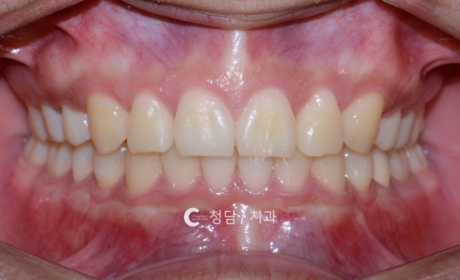

오픈바이트와 삐뚤빼뚤한 치열을 동반한 환자로, 웃을 때 앞니가 닿지 않고 상악 치열이 돌출된 상태였습니다. 정밀 진단 후 하악은 유지하고, 공간 확보와 전치부 배열 개선을 위해 상악 소구치만 발치를 진행하였습니다. 치료 후 앞니가 정상적으로 맞물리며 오픈바이트가 개선되었고, 치열도 가지런해져 심미성과 기능이 함께 회복되었습니다.